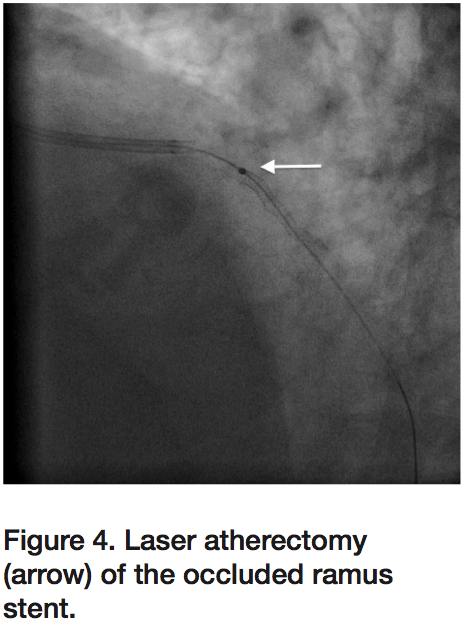

As the patient was being transferred off the procedure table, he once again developed severe chest pressure and recurrent lateral ST elevations. Angiography again demonstrated 100% thrombotic occlusion of the RI at the proximal edge of the previously placed stent (Figure 6), despite a repeat ACT of 337 seconds. Intravenous eptifibatide was initiated in addition to bivalirudin infusion. Aspiration thrombectomy was performed with multiple passes using an Export catheter followed by IVUS, which again confirmed adequate stent

apposition (Figure 7) with good angiographic result and TIMI-3 flow without evidence of dissection or thrombus. The patient’s chest pressure resolved and ST segments normalized, and he was transferred to the ICU with no further episodes of chest pain. Eptifibatide and bivalirudin were continued for 24 hours, and clopidogrel substituted with prasugrel. A hypercoagulable work up eventually demonstrated that the patient was positive for lupus anticoagulant and he was diagnosed with antiphospholipid antibody syndrome (APS). The patient was transitioned to warfarin and discharged home once international normalized ratio (INR) was therapeutic. Discharge medications included aspirin, prasugrel, and warfarin.